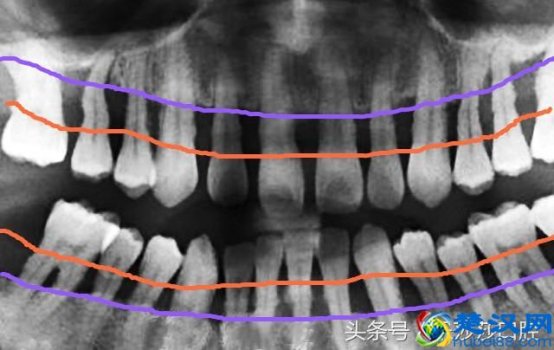

牙周炎能治好吗(得了牙周炎怎么办)

牙周炎能治好吗(得了牙周炎怎么办)说到牙周炎,小编颇有感慨!牙周病患病率在我国比较普遍高达「90%以上」,以35岁以后较为常见。不过遗憾的是,我们国家整个大众口腔卫生的「自我保健意识」还是比较低的,不重视的后果就是牙根暴露,牙齿松动甚至不得不拔掉牙齿。.....[详细]